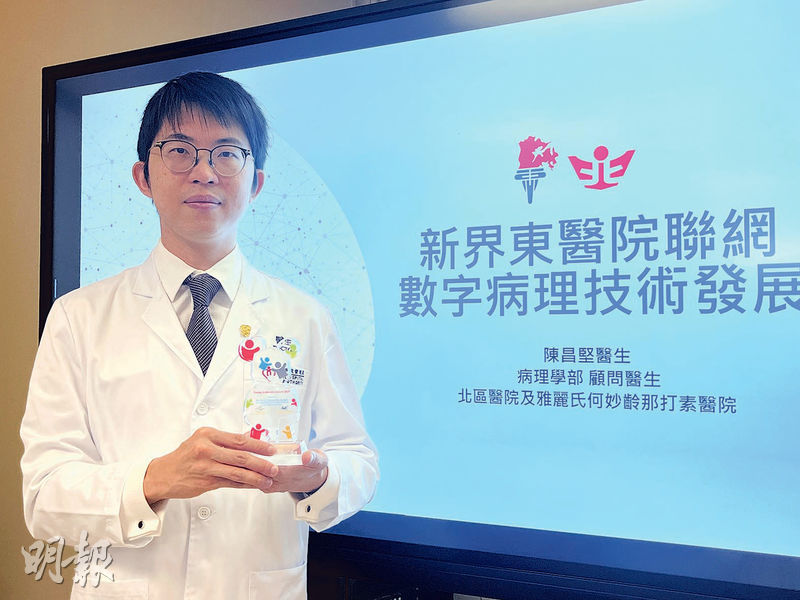

新東聯網首推遙距切片診斷 傳送電子圖像 病理醫生免跨院處理

【明報專訊】新一份《施政報告》提出引進數字病理學技術及人工智能(AI)的應用。新界東醫院聯網推行全港首個遙距病理冷凍切片服務,前年起透過將病人樣本轉化成電子圖像等技術,讓北區醫院病理科醫生可遙距為大埔那打素醫院做副甲狀腺切除手術即場冷凍切片診斷,毋須再親身跨院處理,並正計劃擴展手術種類。兩院亦正試行以AI輔助為乳癌及前列腺癌樣本診斷,預計明年2至3月開始正式使用。

北區醫院及雅麗氏何妙齡那打素醫院病理學部顧問醫生陳昌堅說,遙距切片及診斷時間約20至25分鐘,時間與以往分別不大,但可省卻醫生來回的交通時間。他說目前術中即場診斷中,一半是副甲狀腺切除手術,故因應需求先實行,今年底至明年起兩院亦會開展為皮膚癌患者「邊緣切片」檢測。

陳昌堅表示,開展「遙距病理冷凍切片技術」時,北區醫院已設立工作流程(SOP),但技術仍待創新科技署「香港實驗所認可計劃」認證,預計未來將有監管措施出台。